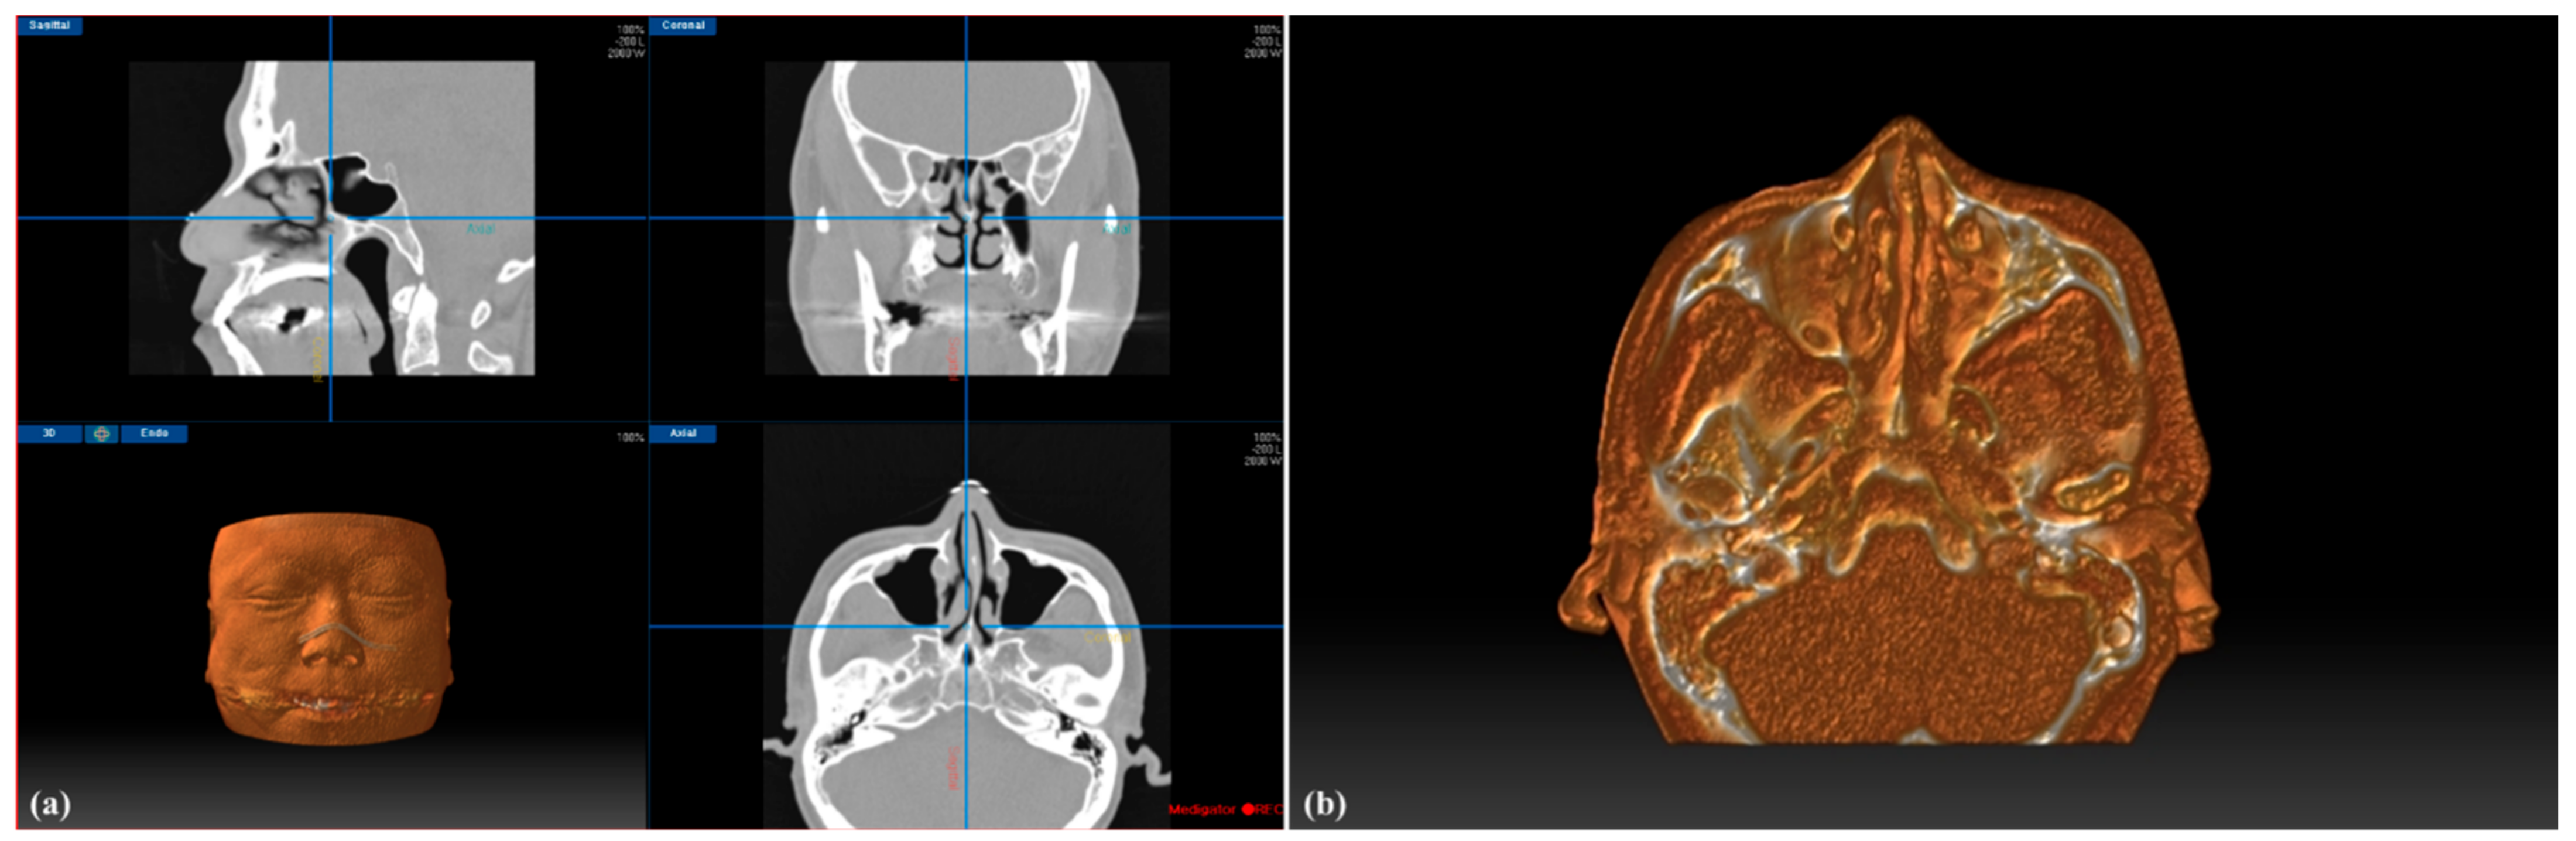

2.3. Image-Guided Endoscopic Sinus Surgery System with 3D Volumetric Visualization

2.5. Image-Guided Endoscopic Sinus Surgery System with 3D Volumetric Visualization